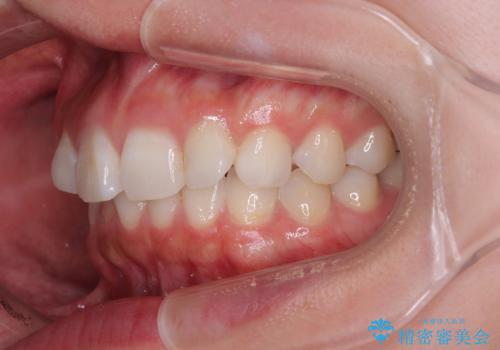

- 前歯のデコボコと突出感を気にして来院された患者様です。

極力目立たない装置を希望とのことで、インビザラインを用いて非抜歯で矯正治療を行うこととしました。

事前に親知らず2本を抜歯し、多少歯列を後方に移動できるように準備をした上で、なるべく歯と歯の間を削ることなくデコボコを解消できるように計画しました。

前歯の捻れを改善するとともに、口元が少しでも引っ込むように治療計画を立て、仕上げることができました。